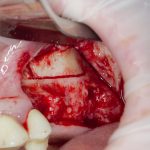

Кстати, обрати внимание на ширину альвеолярного гребня (левая картинка). Она чуть меньше 3 мм. Это объясняет, почему я засомневался в возможности установки имплантатов одновременно с остеопластикой. Понятно и без КЛКТ.

Наперво, мне нужно удалить разрушенный зуб и получить костный аутотрансплантат.

Для получения костного блока, мы открываем донорскую зону, наружную косую линию нижней челюсти.

Получение костного аутотрансплантата.

Здесь потребуется пародонтологический зонд с миллиметровой разметкой или какой-то другой измерительный прибор (операционная линейка). Ранее по КЛКТ я измерил костный дефект, теперь нужно нанести границы будущего костного блока на донорскую зону.